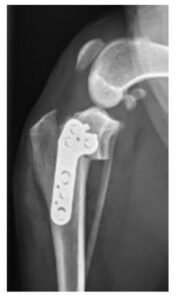

症例1. TPLOを実施した症例(7歳、ビーグル、9 kg)

| 治療前(側方像) | 治療後(側方像) | 治療前(前後像) | 治療後(前後像) |